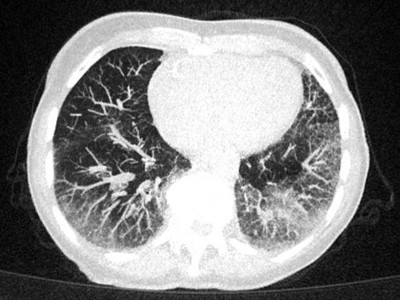

Herpes Zoster am Rücken/© Mumemories / Getty Images / iStock (Symbolbild mit Fotomodell), CT einer Lunge mit Milchglastrübungen/© Kremer P et al. / all rights reserved Springer Medizin Verlag GmbH, Perturbationslaufband (MediTouch BalanceTutor™ BT100, Tnuvot, Israel)/© Haug V et al. | all rights reserved Springer Medizin Verlag GmbH, Tee aus Linghzi-Pilzen/© krungchingpixs / Getty Images / iStock, Eine ältere Frau schaut in die Ferne/© RgStudio / Getty Images / iStock (Symbolbild mit Fotomodell), Einer älteren Frau im Rollstuhl wird der Blutdruck gemessen/© David L / peopleimages.com / Stock.adobe.com (Symbolbild mit Fotomodell), Älterer Mann schaut kritisch auf Tabletten/© Mediteraneo / stock.adobe.com (Symbolbild mit Fotomodell), Alte Person hält Wasserglas in der Hand/© Mike Fouque / stock.adobe.com (Symbolbild mit Fotomodell), ZFA TALKS - Demenz/© (M) Alican Lazutti / Getty Images / iStock (Symbolbild mit Fotomodell) Logo: Springer Medizin Verlag GmbH, Tabletten auf einem EEG-Befund/© Attila Barabas / Getty Images / iStock, Basiskurs Geriatrie, Frau hält sich den linken Fuß/© toa555 / stock.adobe.com (Symbolbild mit Fotomodell), Transrektale MRT/© Springer Medizin, Lila-gefärbter Urin in einem Katheterbeutel/© Franzoi M et al. / all rights reserved Springer Medizin Verlag GmbH, Nach außen rotierter Fuß nach Oberschenkelhalsfraktur/© A. Schuh, Gleise in der untergehenden Sonne/© sanderstock / stock.adobe.com, Älter Frau misst bei älterem Mann Blutzucker/© Vladimir Vladimirov / Getty Images / iStock (Symbolbild mit Fotomodell), Ältere Frau am Tisch misst Blutzucker/© Dragica / stock.adobe.com (Symbolbild mit Fotomodell), Geographische Atrophie/© Augenklinik der LMU München, Ultraschalluntersuchung der Niere/© Your_Photo_Today (Symbolbild mit Fotomodellen), Älterer Mann spricht mit jüngerer Frau/© Photodjo / Getty Images / iStock (Symbolbild mit Fotomodellen), Search Icon, Kleinkind rennt draußen, während es in die Luft zeigt/© William / Adobe Stock, Teaserbild HPV-Impfung für Erwachsene – eine Rechnung die aufgeht!/© syedfahadghazanfar / shutterstock, Neuer Inhalt/© MKC / shutterstock, Teaserbild OA Wörwag Zink/© Tondone | AdobeStock